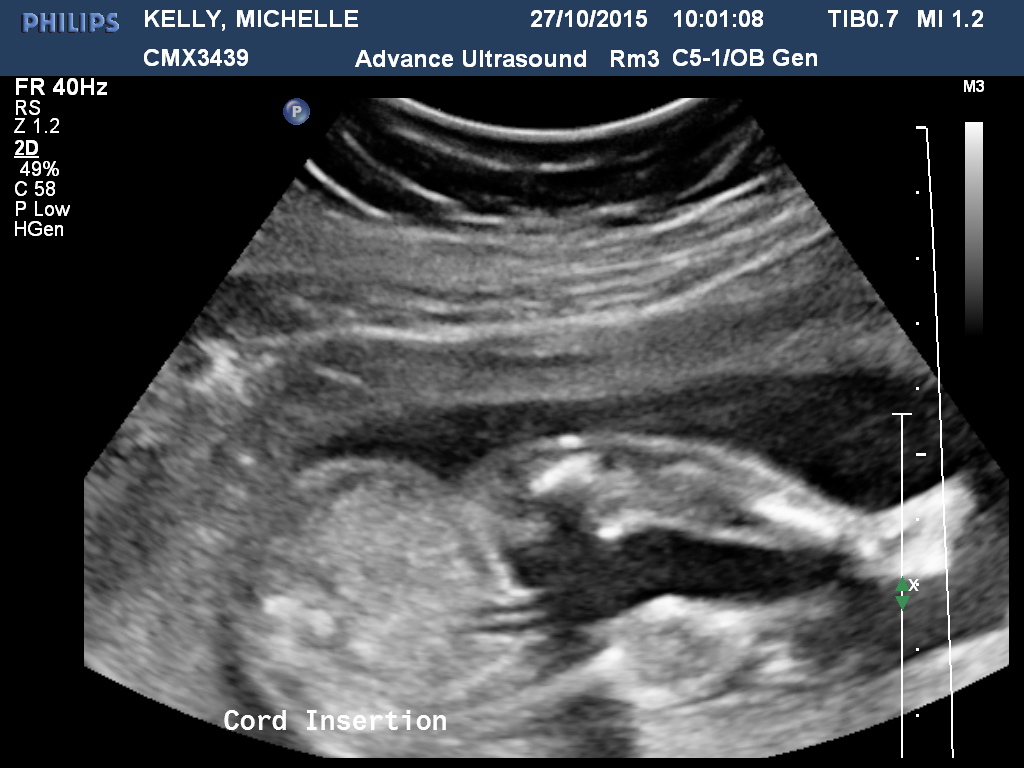

Just had our 20week scan. DH doesn't want to know the gender but I am far too impatient. Hoping I can upload a few pics and you guys might be able to see something I can't ;)

Im no expert but first pic looks girly 😄

Though on 2nd look that may be the cord so im not sure 😮

Yes that's the cord insertion. I don't see any clues sorry.

Just realised it said this at the bottom of the pic lol

I see girl for sure in the first one (3 lines)!!!

Girl